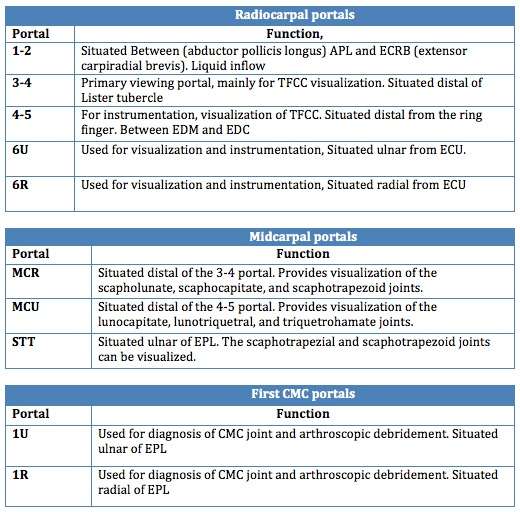

A patient may suffer from various illnesses regarding the wrist. Examples include TFCC lesion, scapholunate and lunotriquetral instability, ganglions, and synovitis. These illnesses concern many different tissues and structures. By using just one portal, one will never be able to visualize all these structures and tissues. For that reason, several portals exist, each having its own function (Table 1).[5] The traditional portals are at the back of the hand (dorsal side), because many neurovascular structures are at risk at the palmar side of the hand.

Dorsal Radial portals The portals lay between the dorsal extensor compartments.[6]

1-2 portal:

- Between the 1st and 2nd extensor compartments

- Located in the Anatomical snuff box

- not often utilized

3-4 portal:

- between the 3rd and 4th extensor compartments

- Located distal to Lister's tubercle

- primary viewing portal

4-5 portal:

- Between the 4th and 5th extensor compartments

- mainly for instrumentation and visualization of TFCC

6R portal:

- at the Radial side of the extensor carpi ulnaris (ECU)

- For TFCC repair

6U portal:

- Located at the Ulnar side of the extensor carpi ulnaris (ECU)

- For TFCC repair

Volar radiocarpal(VR) portal

- This portal is used for evaluation the dorsal radiocarpal ligament(DRCL) and the scapolunate interosseus ligament (SLIL)

Midcarpal portals:

Midcarpal Radial portal (MCR)

- Allows visualization of the scapholunate(SL), scaphocapitate(SC) and scaphotrapezoid(ST) joints.

Midcarpal Ulnar portal (MCU)

- Allows visualization of the lunocapitate(LC), lunotriquetral(LT) and triquetrohamate (TH)joints.

Dorsal Distal Radioulnar joint portal (DDRUJ)

Volar Distal Radioulnar joint portal (VDRUJ)

- Used for assessing the TFCC attachment